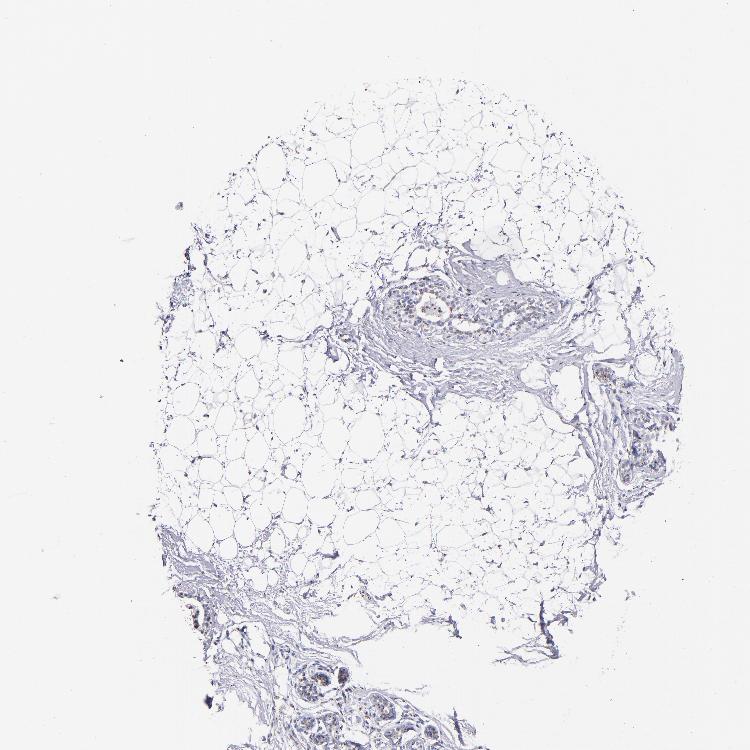

ADIPOSE TISSUE - Antibody stainingi

Antibody staining in the annotated cell types in the current human tissue is reported as not detected, low, medium, or high, based on conventional immunohistochemistry profiling in selected tissues. This score is based on the combination of the staining intensity and fraction of stained cells.

Each image is clickable and will lead to virtual microscopy that enables deeper exploration of all samples and also displays staining intensity scores, fraction scores and subcellular localization as well as patient and tissue information for each sample.

Antibody HPA001677Antibody HPA002315

Adipocytes LowLow